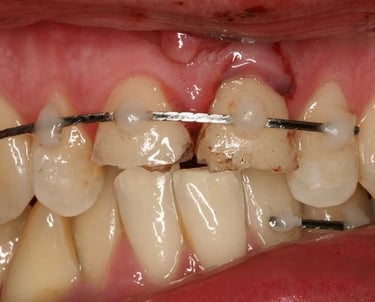

Se maneja el daño causado a los dientes por golpes o accidentes. Puede incluir la reparación de fracturas, el tratamiento de la pulpa y la estabilización del diente afectado.

Tratamiento de traumatismos dentales